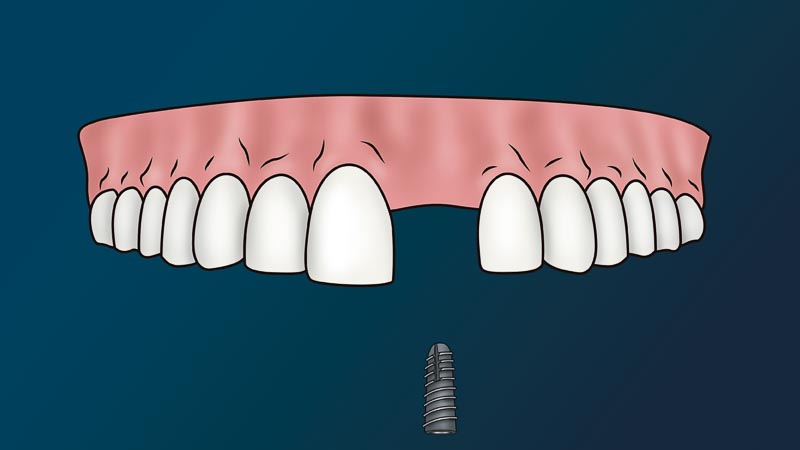

In life, things happen that cause us to have an unhealthy dentition (teeth). Car accidents, falling, work accidents, or simply not growing up with an awareness of proper hygiene, can cause serious health problems later in life. When teeth go missing, some people think that they can leave that space empty without serious health repercussions.

This could not be further from the truth

Since the average human bite can create up to 70 + pounds of force, having a space where a tooth should be can risk displacing healthy teeth. This can even lead to bone loss in that area as well. If this problem is not solved early on, it can cause detrimental problems in the future.

The most viable solution to a missing tooth is to get a dental implant.

What is the Dental Implant Process in Mexico?

The dentist will attach to your jaw a metal root (implant) and place on top a fake tooth (crown). We call this procedure, a dental implant. Since this procedure is non-life threatening and non-essential to one’s immediate health, it considered a cosmetic procedure. In other words, medical or dental insurance policies don’t cover this procedure.